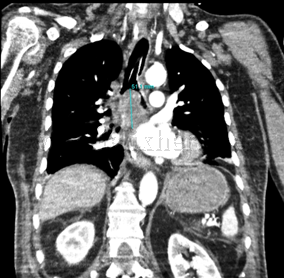

Neoplasia de carina principal